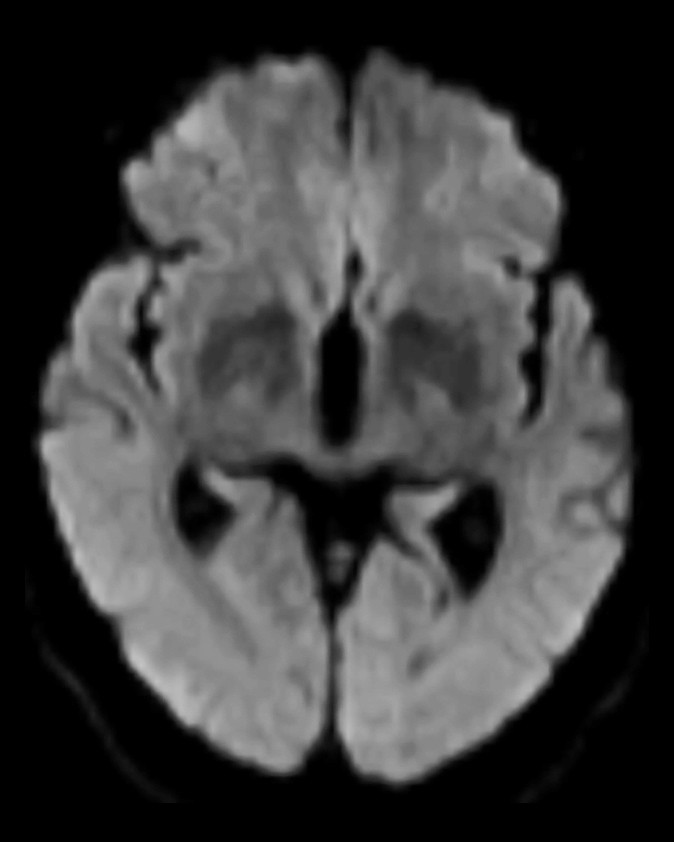

30 minutter etter at hun ble akutt blind, ble det tatt CT caput og CT-angiografi av intrakraniale arterier. CT caput viste utbredt diffus kontrastoppladning i synsbarken (oksipitalt) bilateralt, men ingen blødning eller infarkt (figur 1). CT-angiografi viste ingen karokklusjon eller karspasmer. Som forventet ved en kranial dural arteriovenøs fistel var det økte kartegninger og arterialisert kontrastfylning i durale vener.

MR caput (T1- og T2-vektede sekvenser, FLAIR-sekvenser og diffusjon med ADC-verdier (apparent diffusion coefficient)) utført rett etter CT-undersøkelsen viste som tidligere uspesifikke T2- høysignal lesjoner, men ingen nytilkomne forandringer (figur 2). Det var ingen diffusjonsrestriksjon, som er forventet ved ferskt hjerneinfarkt (3).

På pasientens CT-bilder var det retensjon av kontrast i synsbarken på begge sider. CT-bildene var gjort uten kontrast, så den synlige kontrasten måtte være fra konvensjonell cerebral angiografi gjort to timer tidligere. CT-angiografi viste åpne kar. På MR var det ingen nytilkomne signalforandringer. De kliniske symptomene sammen med bildefunnene passet dermed ikke med cerebral iskemi på bakgrunn av tromboembolisme eller karspasmer.

Dette er en eksklusjonsdiagnose. MR caput og eventuelt CT caput med CT-angiografi er indisert for å utelukke blødning eller iskemisk årsak til synsaffeksjon. MR kan være negativ eller vise høysignal på T2- og FLAIR-signaler som ved vasogent ødem. CT kan vise normale funn eller kontrastoppladning oksipitalt. CT-angiografi fremstiller åpne kar uten spasmer.